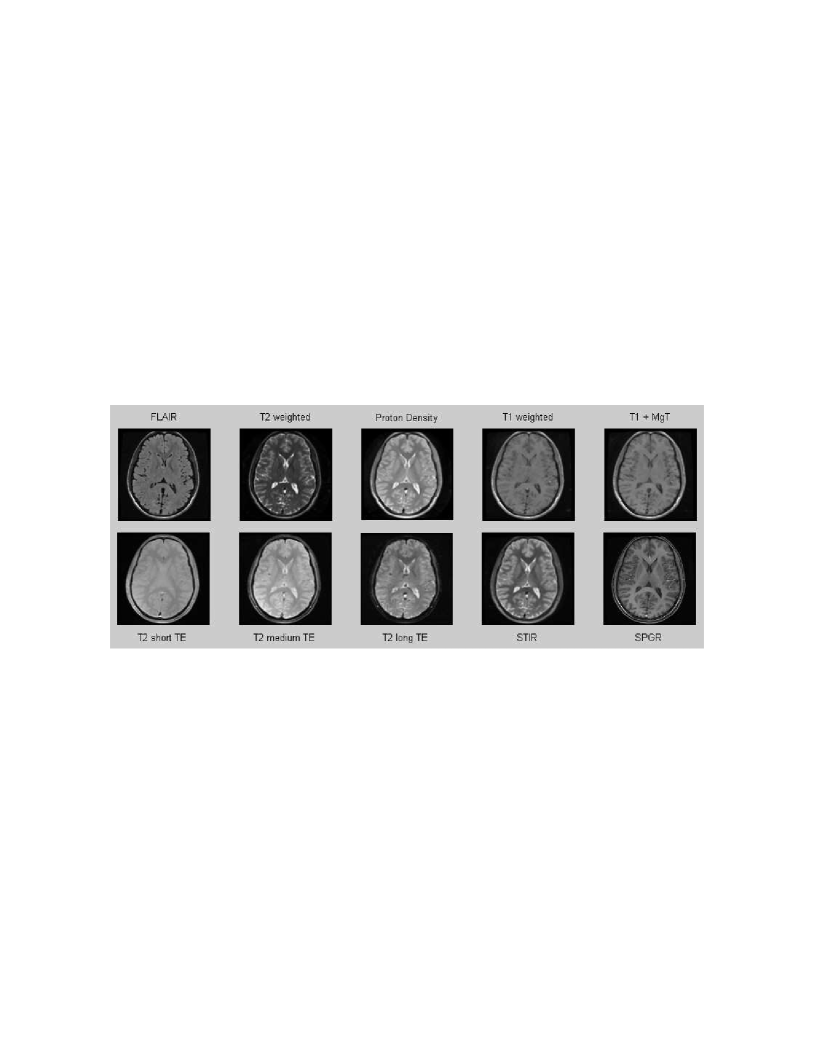

In this thesis, a novel coherent integrated methodology is introduced (theory, algorithm and applications) to reduce the dimensionality of high-dimensional datasets. The method constructs a diffusion process among the data coordinates via a random walk. The dimensionality reduction is obtained based on the eigen-decomposition of the Markov matrix that is associated with the random walk. The proposed method is utilized for: (a) segmentation and detection of anomalies in hyper-spectral images; (b) segmentation of multi-contrast MRI images; and (c) segmentation of video sequences.

This thesis is composed of three parts. In the first part, we introduce the novel Diffusion Bases methodology (theory, algorithms and applications) for dimensionality reduction. Specifically, in Chapter 2 we give an in depth introduction to dimensionality reduction where we provide a formal definition of the problem followed by a description of the current state-of-the-art techniques for dimensionality reduction. In Chapter 3 we describe in details the diffusion maps technique [45] since it is closely connected to our diffusion Bases (DB) dimensionality reduction scheme which we introduce in Chapter 4. The DB algorithm explores the variability among the coordinates of the original data while the DM explores local neighborhoods of points in the dataset. Both algorithms use a random walk model. The DB algorithm uses the eigenvectors of the corresponding Markov matrix as an orthonormal system and projects the original data onto it to obtain the low-dimensional representation. The DM algorithm, on the other hand, builds a different Markov matrix whose eigenvectors constitute the low-dimensional representation. In Chapter 5 we provide an introduction to hyper-spectral imagery which includes the terminology, concept, motivation and common applications in this area. Chapter 5 is necessary for the understanding of Chapters 6 and 9. Chapters 6-8 include successful applications of the DB scheme. Specifically, in Chapter 6, the DB dimensionality reduction scheme is used for segmentation of hyper-spectral images and for the detection of anomalies in images of this type. In Chapter 7, the DB scheme is incorporated in an algorithm for segmentation of multi-contrast MRI images. Segmentation of video sequences which uses the DB scheme is described in Chapter 8.